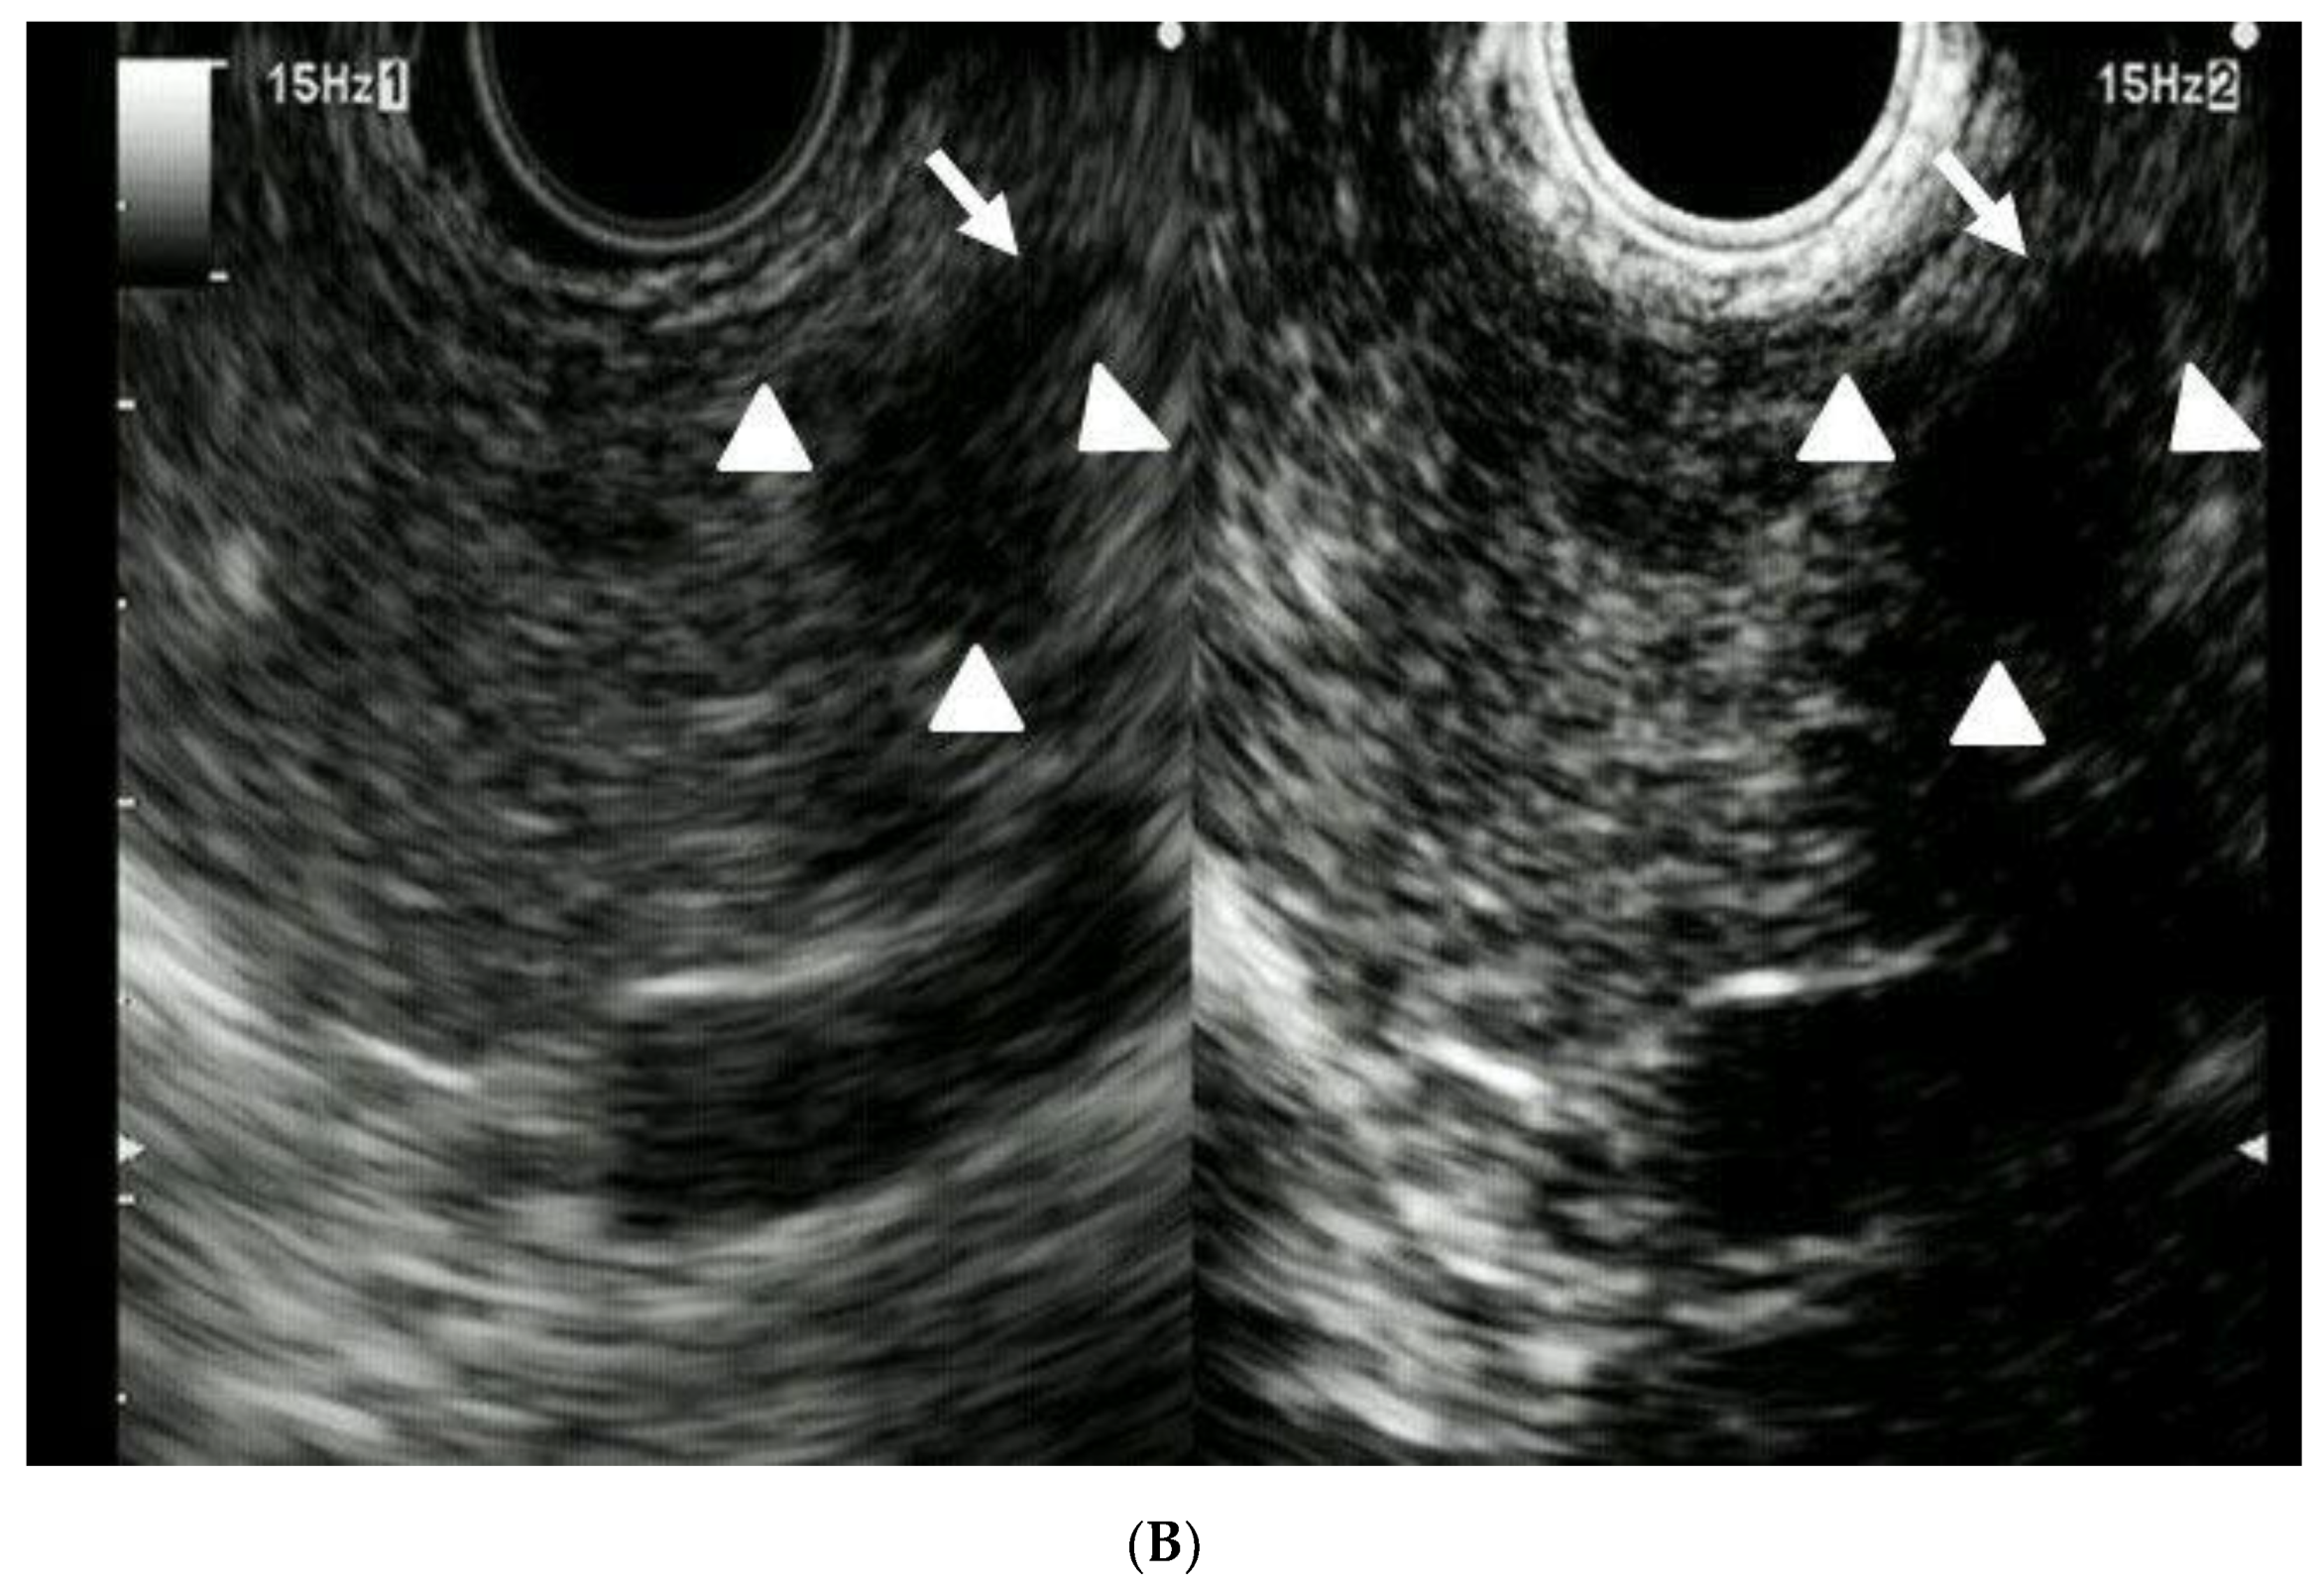

Utility of Contrast-Enhanced Harmonic Endoscopic Ultrasonography for Early Diagnosis of Small Pancreatic Cancer